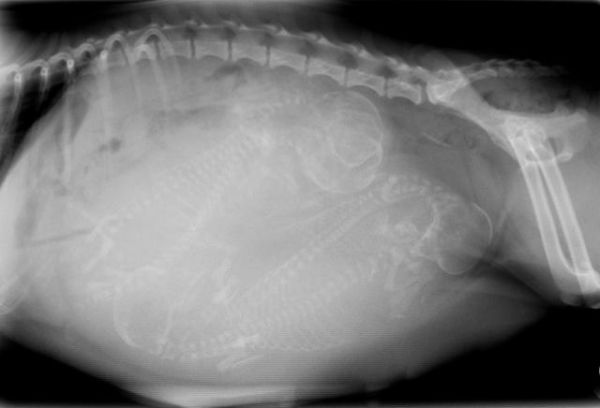

小狗的眼睑在第32天左右开始形成,第35天左右形成脚趾,第40天左右行成爪子,大约第45天左右形成外形和骨架。第50天后,医生可以进行X光检查小狗的头部数量,并形成一个准确的数字,预计产后狗狗的数量,到第58天左右,幼犬基本完全形成。

第二阶段:狗狗开始分娩,整个过程最长的可能要24小时。通常母犬每隔30-60分钟就会产下一只小狗,根据不同的母犬,时间会有差别,但最长间隔不会超过2小时,所以通过之前宠物医生对母犬进行X光检测小狗的数量,在这一阶段小狗是否出生完,就很容易判断了。